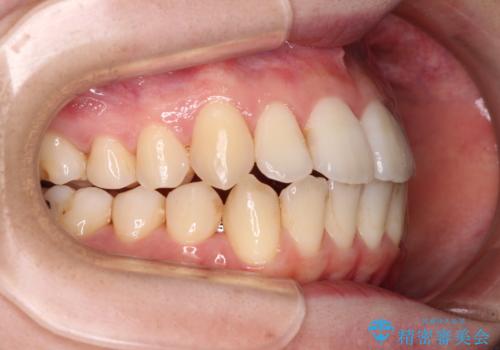

【モニター】前歯の前突感とクロスバイトをインビザラインで改善

- 前歯の突出感とクロスバイトが気になり、インビザラインによる矯正治療を希望して来院された患者様です。

上顎側切歯(上の真ん中から2番目の歯)が舌側転位している場合、インビザラインでは仕上げきれないことが多く、更には無理して動かそうとすると歯髄壊死を起こすリスクが高いと言われています。

インビザラインで歯列を移動する前に、上顎前歯をワイヤー矯正で整え、その後上下歯列をインビザラインにて矯正治療を行うこととしました。

舌側転位している側切歯特有の、切縁の位置が不揃いであったり、根元が内側に引っ込んだ状態であったりという、インビザライン独特の仕上がりになることなく、きれいに整った歯列とすることができました。